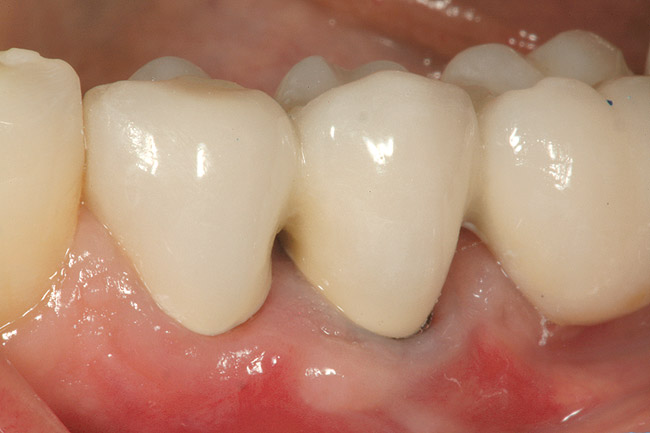

Figure 11  The all-ceramic restorations (Venus‚Ñ¢ porcelain, Heraeus Kulzer, Inc, Armonk, NY) in place at the delivery appointment. (Ceramic artistry performed by Mr. Vincent Devaud, CFC, MDT, Pasadena, CA.)

Figure 11

Figure 12  Six months after surgery, the patient‚Äôs full smile showed improvement in gingival symmetry and the gingival papilla between tooth Nos. 8 and 9 had completely reoccupied the gingival embrasure space.

Figure 12